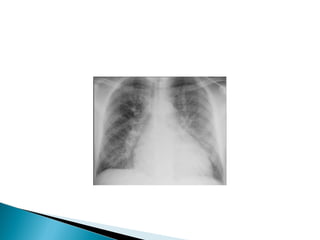

 Acute pulmonary oedema

 Pneumonia

 Acute pulmonaryoedema  Pneumonia